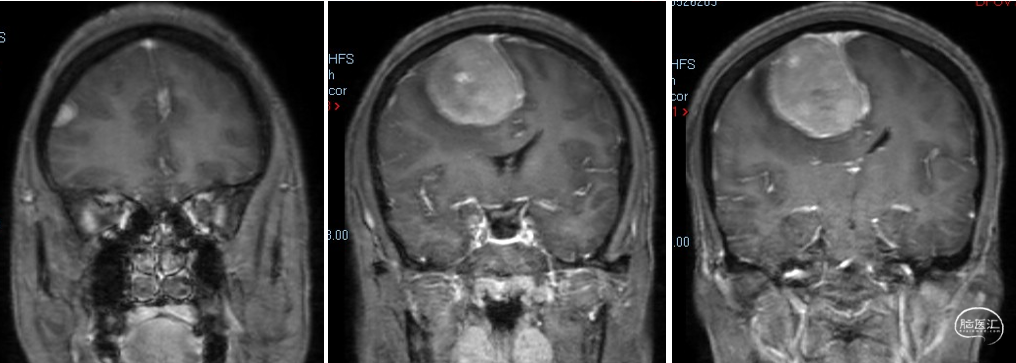

现病史:患者2020年无明显诱因出现头痛,患者未予以重视及相关诊疗。2周前患者出现左侧肢体活动障碍,伴肢体麻木,遂于2023年9月19日就诊于当地医院,行颅脑CT检查示:“右侧顶部大脑廉旁见混杂密度影,边界清,大小约6.0cm×4.4cm,周围见低密度水肿,脑中线左移,脑沟及脑室系统未见特殊,提示:右顶部占位,脑膜瘤可能性大,建议进一步检查”。现为求手术治疗,转至我院。

术前诊断:颅内多发脑膜瘤(右额顶部窦旁及右额部)。

手术方式:右侧额部及窦旁脑膜瘤切除术。